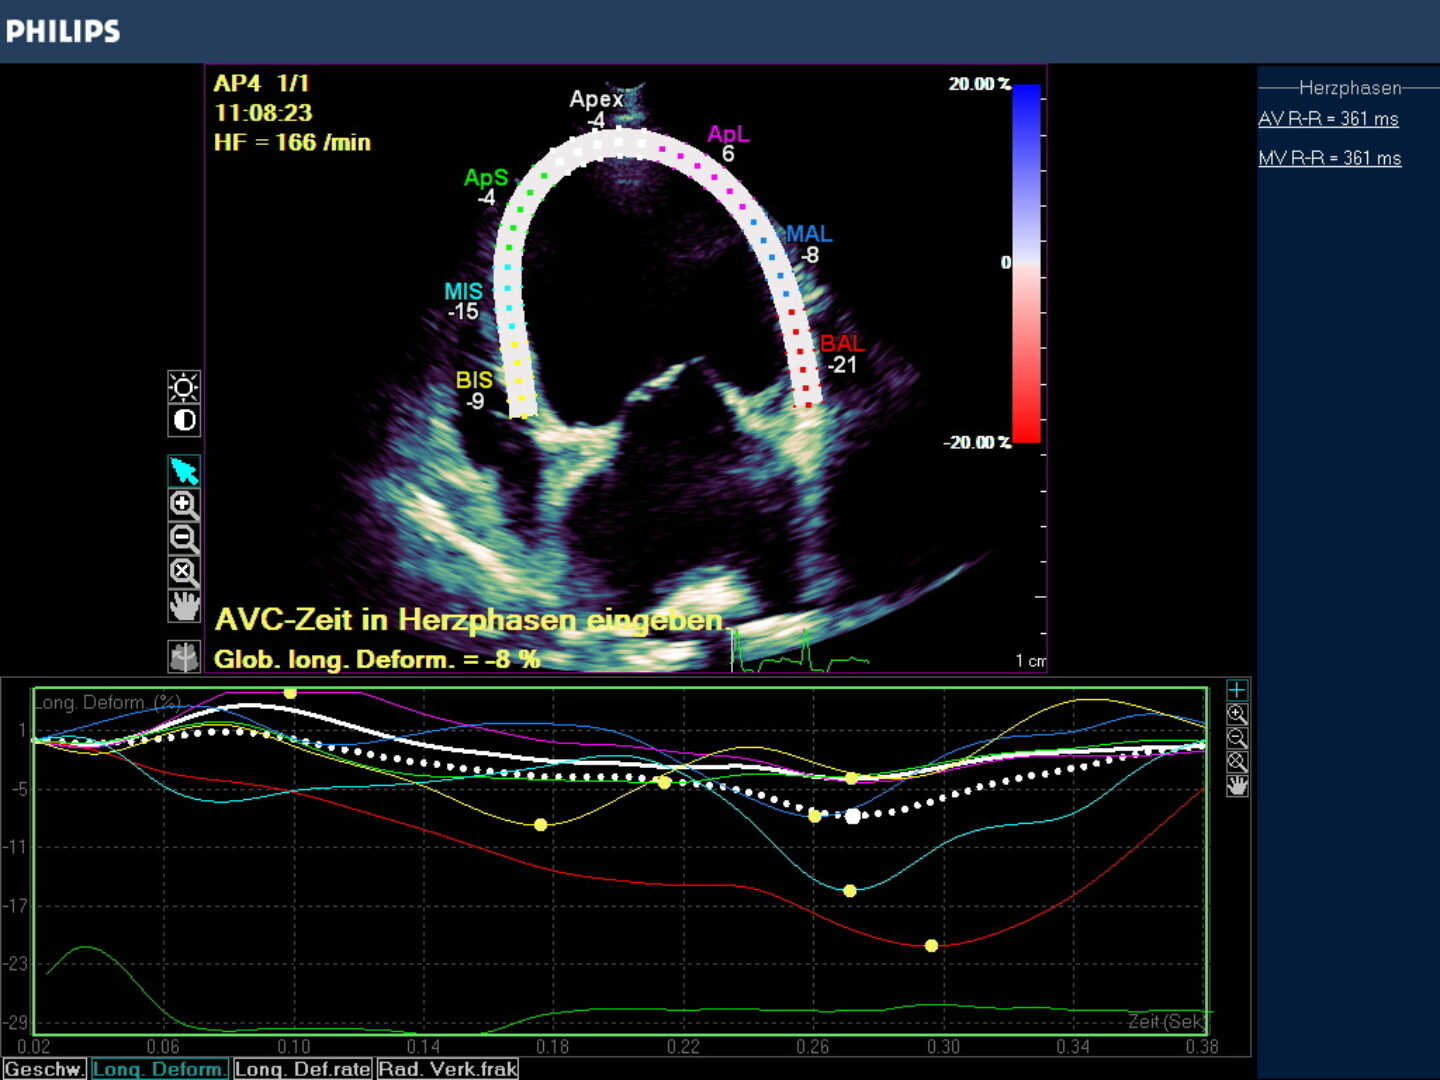

In praxi wird das Myokardium (LV/RV oder Atrien) in 7 Segmente unterteilt, die z.B. für den linken Ventrikel eine Hufeisenform annehmen, die Grenzen dieser enddiastolischen Region Of Interest (ROI) können manuell korrigiert werden über die Software des Geräts. Erfasst wird die endokardiale -, epikardiale Grenze und die myokardiale Mittellinie. Die Akquise der Werte erfolgt automatisch, semiautomatisch oder manuell. Die Einbeziehung des Perikardiums kann zu einer Reduzierung der Strainwerte führen! Die ROI Segmente bekommen Farben und Kürzel zugeordnet (Tabelle 1, Abb.2), die für Myokardsegmente stehen und so können nicht nur globale sondern auch regionale Dysfunktionen erkannt werden.

Der Gerätemonitor gibt die Strainmessergebnis in Form einer Kurve an , deren wellenförmige Line den Farbsegmenten entspricht und die zeitliche Veränderung der Strain beurteilbar macht. Jede ROI hat auch hier ihre definierte Farbe und der Durchschnittswert wird in einer globalen Strain Kurve als weiße Punktlinie angezeigt. Der Anteil der einzelnen Segmente an der GS ist abhängig von ihrer Größe. Das Maximum der globalen Strain GS wird als globale longitudinale Strain definiert (GLS).

Das Ergebnis der GLS wird in negativ -%- Zahlen angegeben. In besonders schwer erkrankten Fällen kann die Zahl positiv werden! Je höher die negative Zahl angegeben wird desto stärker ist die Verformung bzw. Kinesie des Muskels. Darüber hinaus wird nach der Simpson Methode eine Ejektionsfraktion ermittelt , die in EF % angegeben wird (Abb. 3).

Globale Dysfunktion des linken Ventrikels durch Dilatation bei einer DKM oder infolge eines Ductus botalli persisitens oder einer chronischen Aorteninsuffizienz können bei hochgradigen Befunden sehr niedrige oder gar positive Strainzahlen hervorbringen. Die Ejektionsfraktion ist in diesen Fällen i.d.R. vermindert (Abb. 3).

Die Wirkung positiv inotroper Medikamente (z.B. Pimobendan oder ß-Metildigoxin) auf den Herzmuskel kann über Speckle Tracking ebenfalls verfolgt werden. Das wesentlich stärkere positive Inotropikum Pimobendan lässt die EF% der Tiere im Vergleich zum Ausgangswert oft deutlich ansteigen. Hunde mit moderat erniedrigter Ejektionsfraktion von z.B. 32% können 60% EF und mehr in Kontrollen erreichen. Das gleiche gilt für eine Zunahme der Strainzahlen im negativen Bereich . Insbesondere bei Grenzfällen in der Therapieentscheidung können mit diesen Messungen Indikationen für positive Inotropika präzisiert werden.